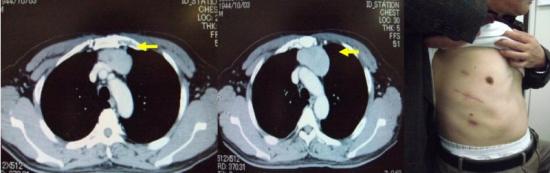

(2)右肺癌+巨大胸壁転移の症例に対して右肺上葉切除+縦隔リンパ節郭清ならびに胸壁転移切除・腹直筋による胸壁再建術(下図)。

胸部 CT:巨大胸壁転移

術中所見:胸壁合併切除 (第6,7,8,9,10肋骨切除)